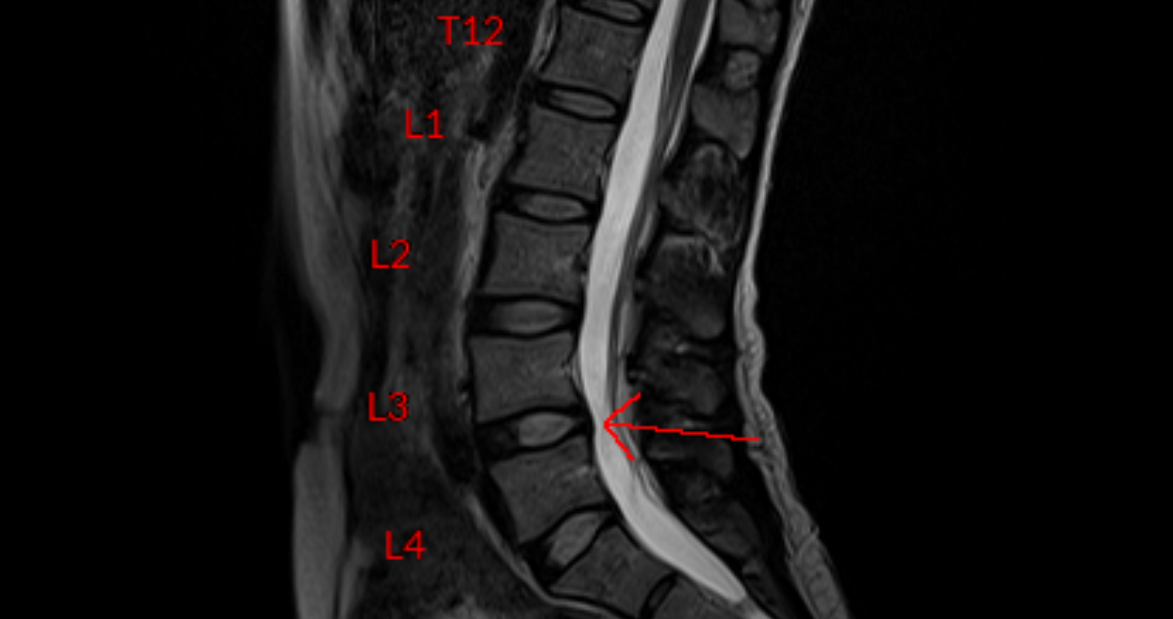

• I have mild degenerative spondyloarthropathic changes to my lumbar spine (L3/L4), and also my cervical spine (C5/C6).  These are common for people starting in their 30s and are irreversible, possibly from sitting too much or sleeping poorly. I am really into bouldering and want to continue, so I'll research how to keep my spine as healthy as possible.

Lumbar scan showing degeneration and lack of L5

• I have 4 lumbar vertebrae as opposed to the normal 5.  There’s nothing in research about the difference in function between numbers of lumbar, which could vary from 4 through 6, but I believe it reduces my lumbar flexibility. I can't do the Navasana yoga pose no matter how much I practice and build ab muscles, so it has to be my bones, man. (My abs are abnormally strong from climbing.)